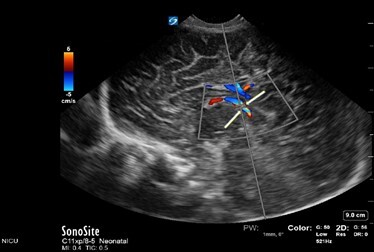

Neonatology Normal Anatomy Too Small Sample Gate Image